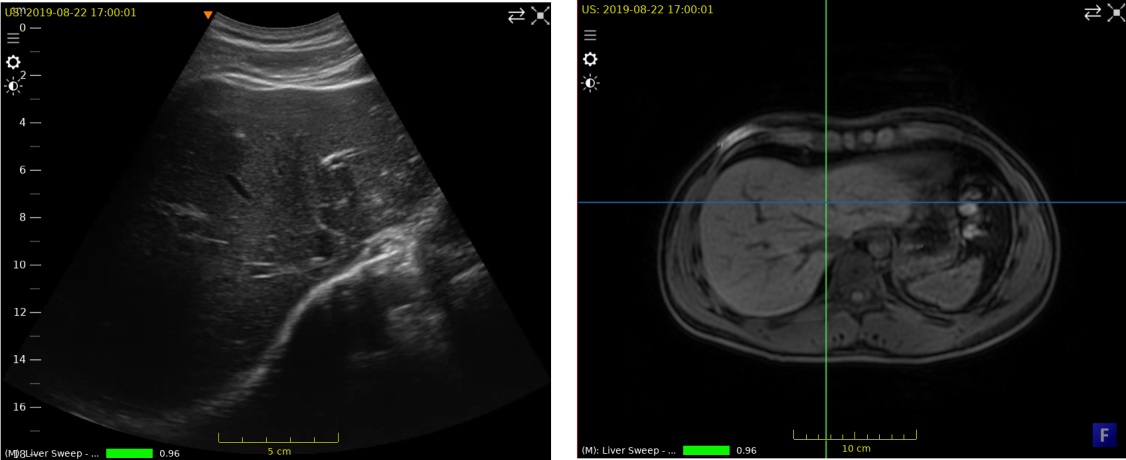

../../_images/US.UltrasoundRegistrationTutorial.exploration01.png

Ultrasound frame (left) and MPR view of the MR volume (right).

Scrolling e.g. to frame 78 in the ultrasound sweep, we will clearly see some liver vessels and the boundary between the liver and surrounding tissues in the 2D view. Scrolling e.g. through MPR view (3a), we will find a similar view of the liver in the MR volume.